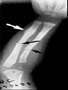

Fracturas en diferentes períodos de consolidación

En este caso se puede observar con flechas negras, fracturas recientes de ulna y radio, Con flecha blanca una fractura de la ulna consolidada, pues presenta callo óseo abundante incluso comenzando el período de recanalización del hueso.